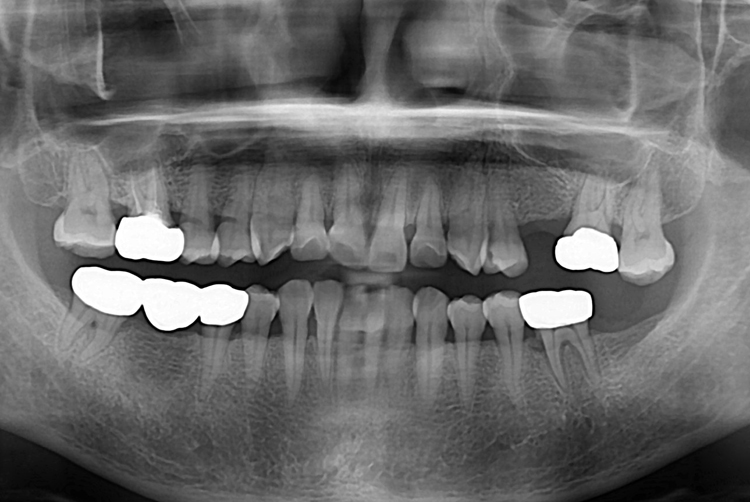

[임플란트] 어금니 임플란트

치료후 : 2018-10-30

세종치과는 많은 환자와 다양한 케이스를 바탕으로

항상 편안한 임플란트 수술을 제공하고자 노력하고,

오래동안 튼튼히 쓸 수 있는 임플란트 수술을 가장 큰 목표로 삼고 있습니다.